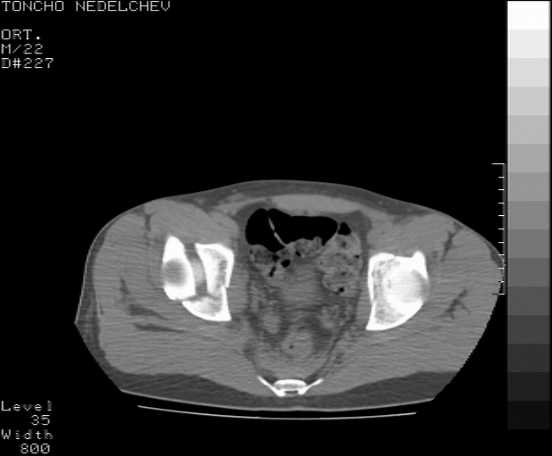

Here are some more axial images. What is your opinion as for the timing of the operative treatment?